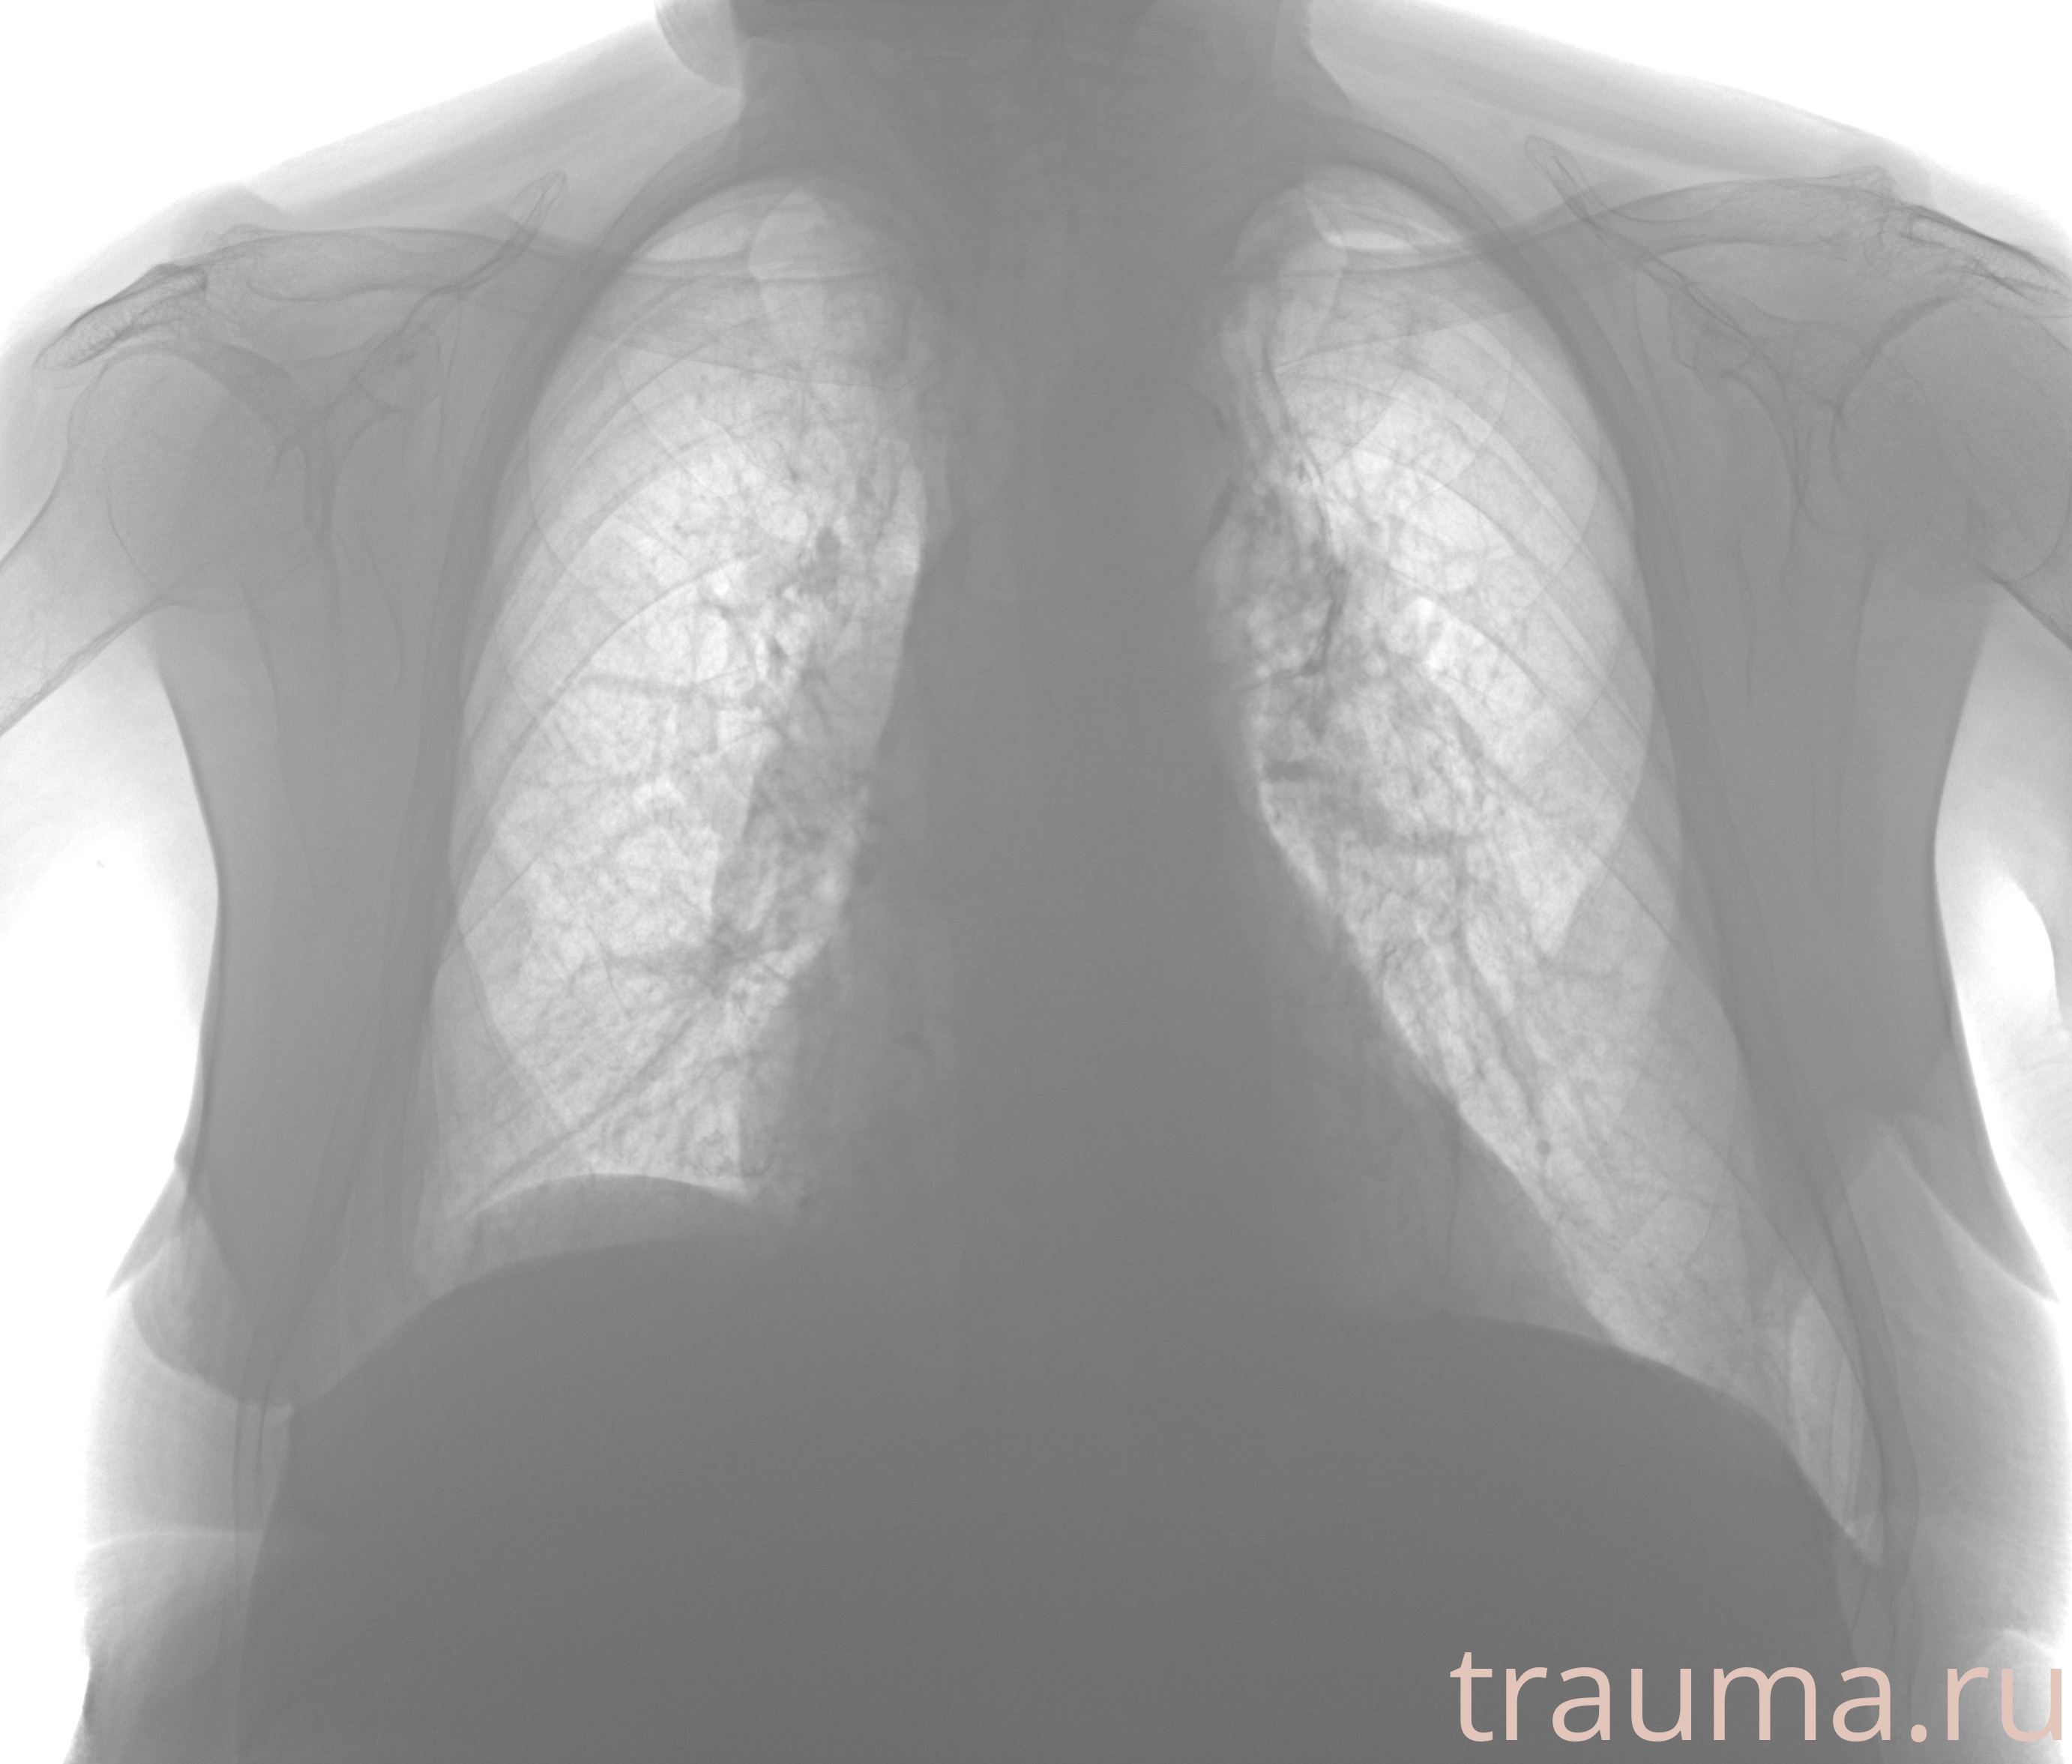

Рентгенограммы

Рентген на дому: по вашему адресу приезжает врач-рентгенолог, травматолог-ортопед с мобильным рентгеновским аппаратом, проводит диагностику травмы или заболевания, делает необходимые рентгенограммы, дает рекомендации по дальнейшему лечению. Получить качественные снимки в домашних условиях возможно благодаря уникальной методике, разработанной МосРентген Центром для института  Склифосовского

при переломе шейки бедра и пневмонии от компании МосРентген Центр - партнера Института имени Склифосовского